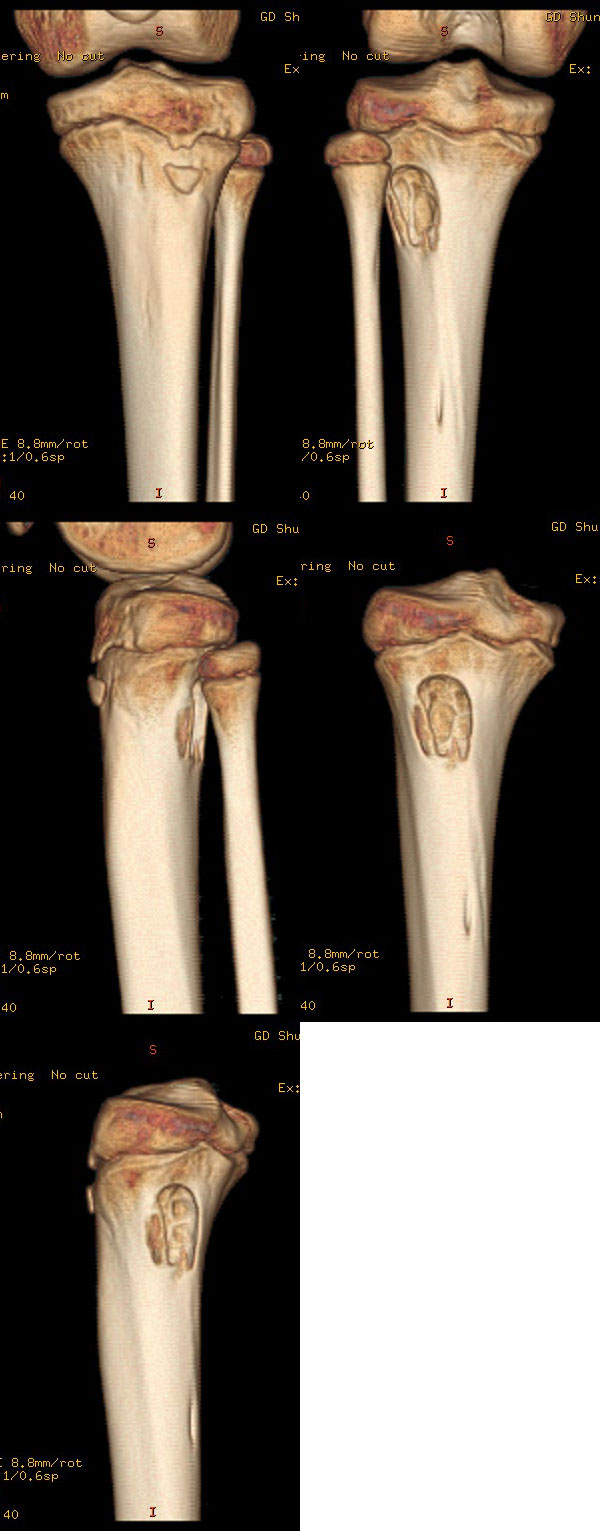

以下是引用37度在2010-1-7 12:22:00的发言:[br]左胫骨上段纤维性骨皮质缺损(非骨化性纤维瘤).

以下是引用dyqct在2010-1-7 14:54:00的发言:[br]考虑为左胫骨上段纤维性骨皮质缺损 ,可自愈.

以下是引用沉默是金在2010-1-8 18:51:00的发言:[br]非骨化性纤维瘤

以下是引用xkncyyhyq在2010-1-7 9:54:00的发言:[br]考虑为纤维性骨皮质缺损